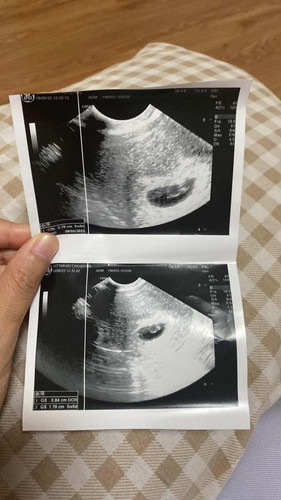

6w6d อัลตร้าซาวด์ทางช่องคลอด

ขออนุญาตสอบถามแม่ๆค่า 6w6d ในภาพอัลตร้าซาวด์ปกติมั้ยคะ เห็นน้องและหัวใจกระพริบ แต่คุณหมอปรับเครื่องฟังหัวใจน้องไม่เป็น 🫣🥹#ท้องแรกคะ

ปกติค่ะ หมอบอกว่าหัวใจคืออวัยวะแรกที่ทำงานเต้นตุ๊บๆ น้องยังเล็กมากค่ะเสียงหัวใจน่าจะยังไม่ได้ยิน